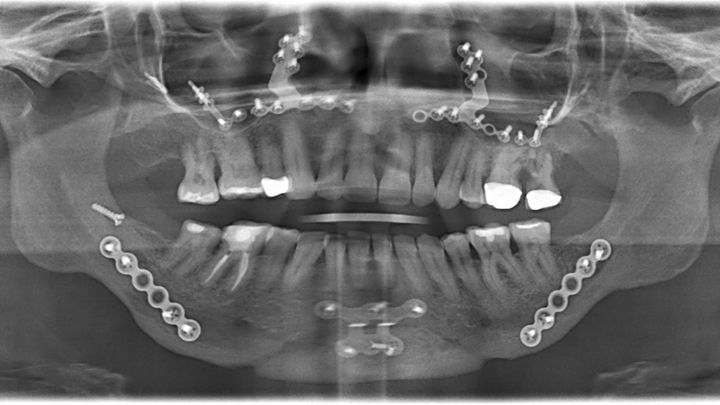

I had double jaw surgery (DJS) on 1/23/20 to correct my sleep apnea. As you can see from the X-ray, there is lots of hardware in my face. That plate on my chin is causing my jaw bone to be infected and eaten away. I need surgery in Boston to remove the chin plate, clear out the infection, perform a bone and gum graft, do a corrective DJS, extract my lower front teeth, get a partial or bridge, and have a rhinoplasty done.

I had double jaw surgery (DJS) on 1/23/20 to correct my sleep apnea. As you can see from the X-ray, there is lots of hardware in my face. That plate on my chin is causing my jaw bone to be infected and eaten away. I need surgery in Boston to remove the chin plate, clear out the infection, perform a bone and gum graft, do a corrective DJS, extract my lower front teeth, get a partial or bridge, and have a rhinoplasty done.